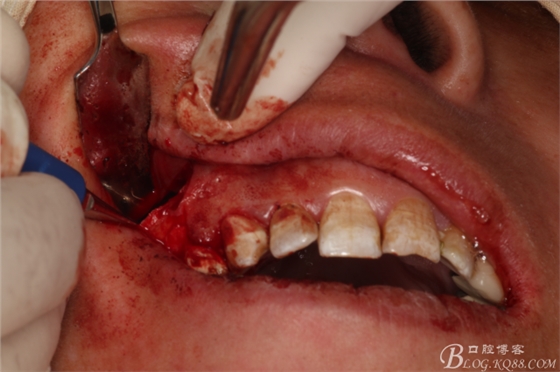

圖13.刮除腭側(cè)牙根周圍病變組織

圖14.切去16近中頰根根尖3mm,并行MTA倒充填